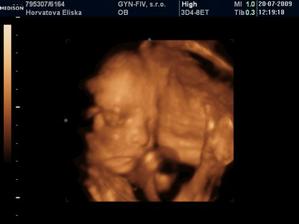

Dvojicky po KET

tak sme sa dockali-nase dvojicky sa narodili v 37+1 tt -20.10.09 cisarskym rezom -11:00 Matúško 3150g a 48cm a 11:02 Natálka 3030g 48cm,